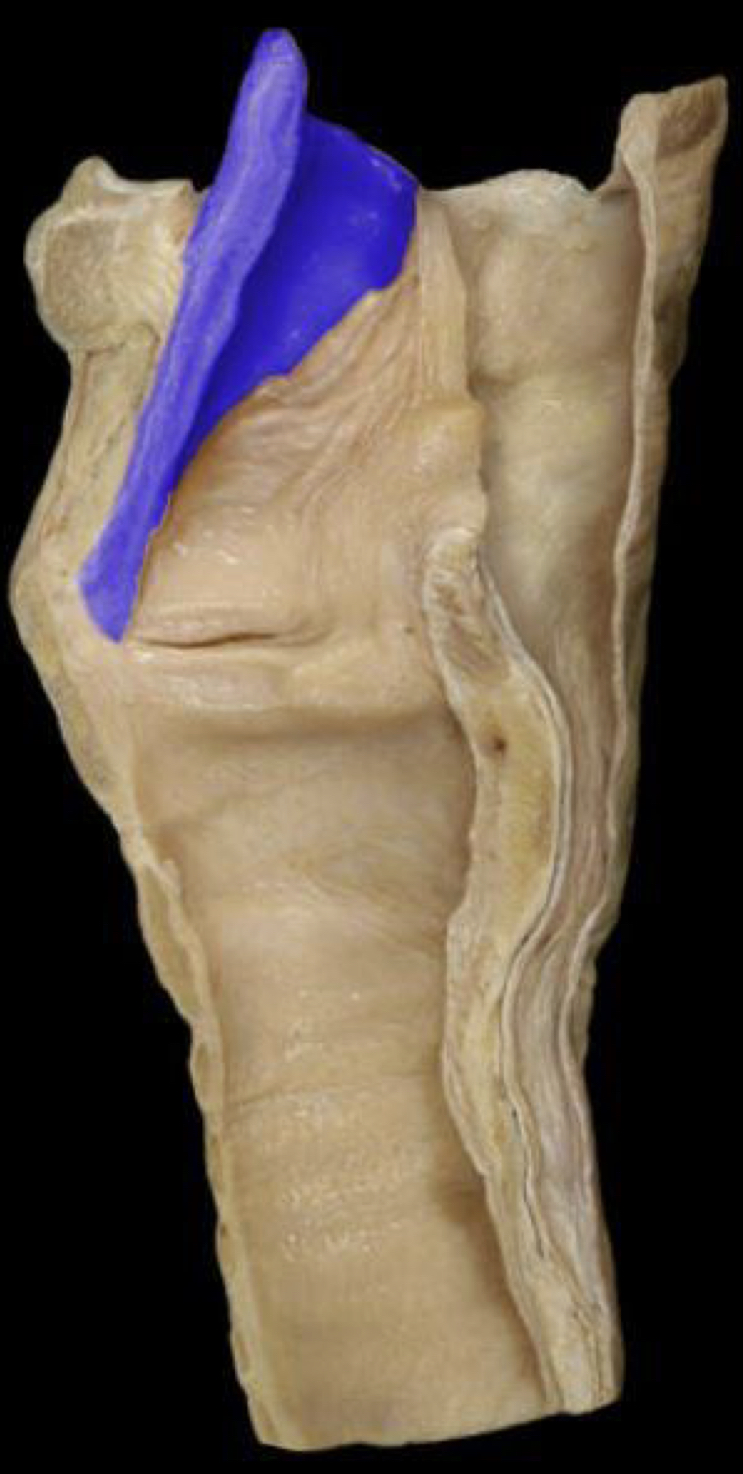

What structure is highlighted in blue?

Epiglottis (lateral view)